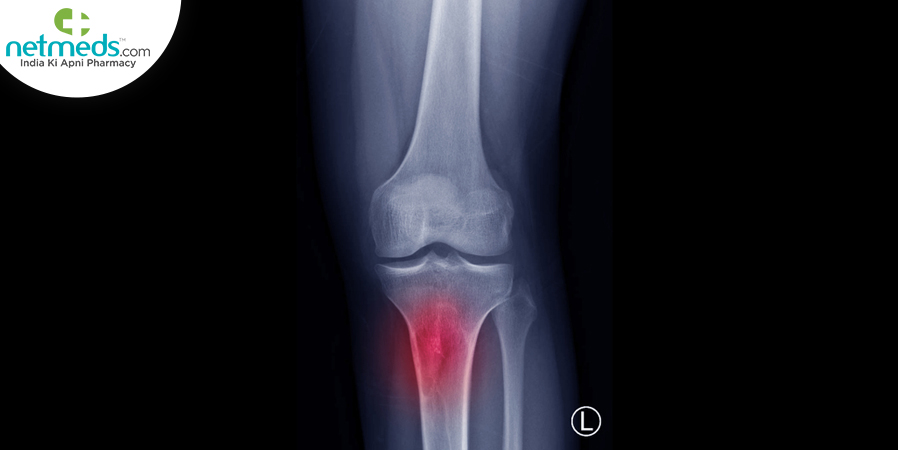

Imaging Tests. MRI or CT scan is also advised to further evaluate the affected bones besides X-rays are done to check and take images of internal tissues, bones, and organs.